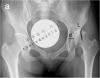

陈晓东教授提供-左侧髋臼发育不良

患者,女性,38 岁。左侧髋臼发育不良。